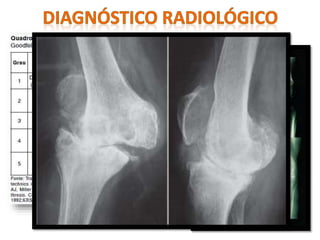

Radiografias

Radiografia

panorâmica de

MMII